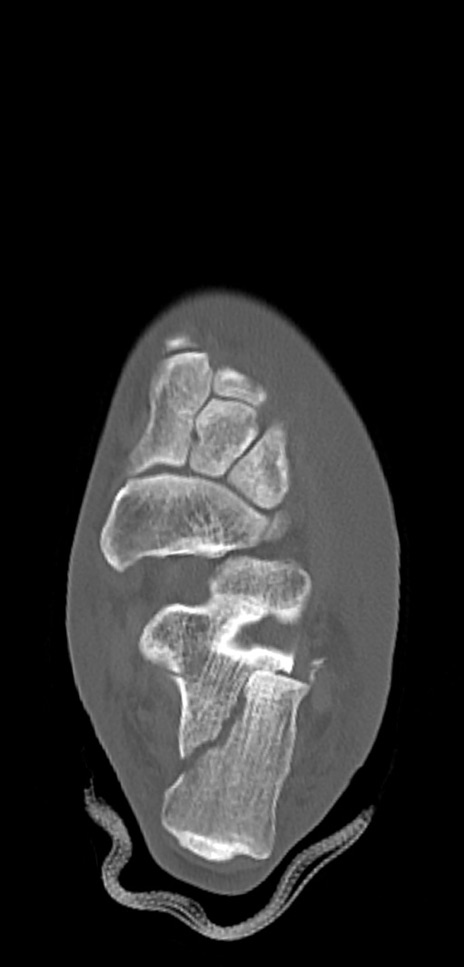

症例37 左足関節CT(横断像)

左足関節CT

冠状断像